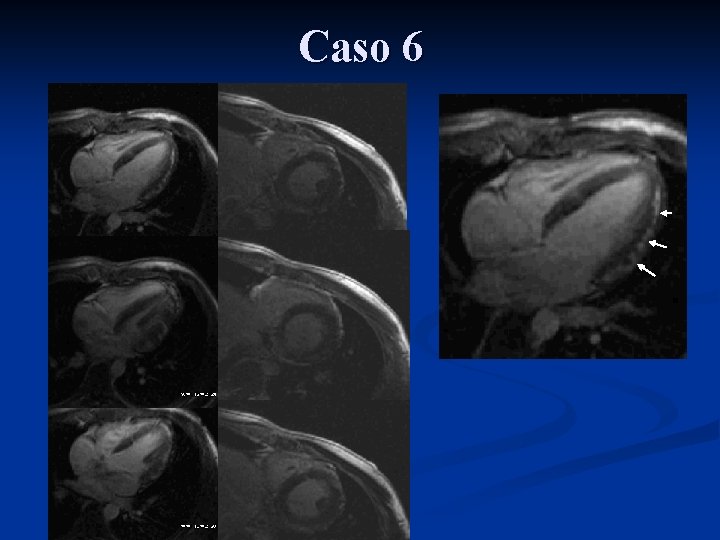

Caso 6